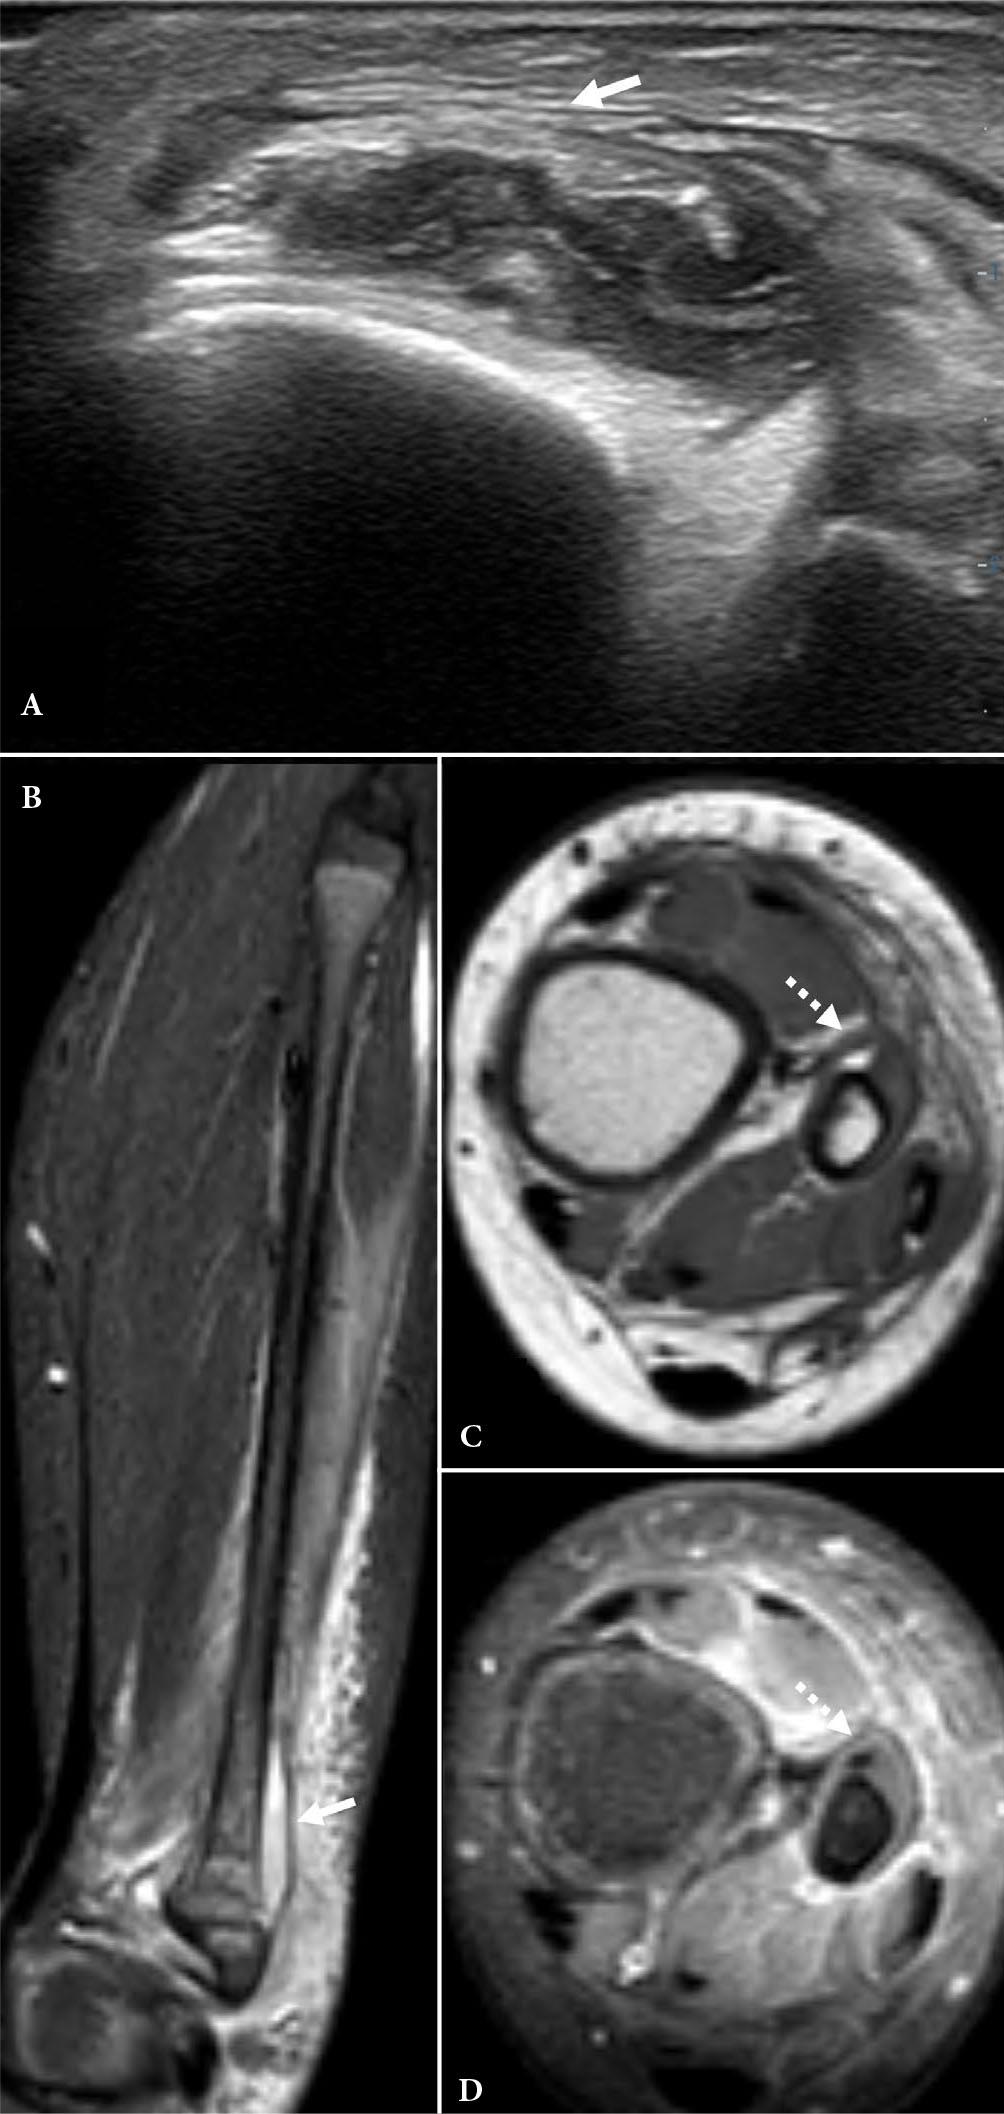

Fig. 4.